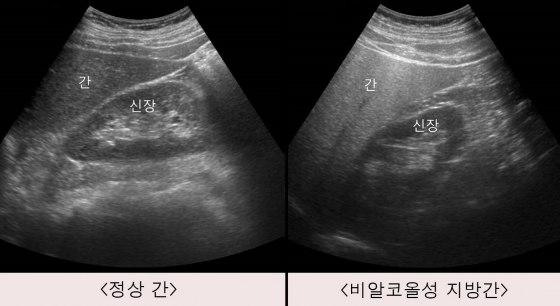

지방간은 말 그대로 간에 지방이 과도하게 쌓인 상태입니다.

정상 간은 지방이 5% 이하인데, 이 수치가 넘어가면 지방간으로 진단돼요.

→ 요즘 비알코올성 지방간이 훨씬 많습니다.